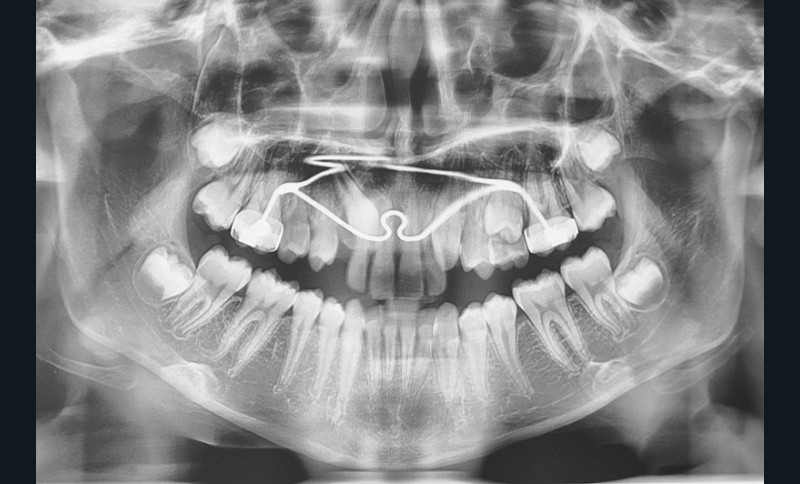

chirurgie à visée orthodontique : extractions de dents de sagesse, dégagement de dents incluses, poses de mini-vis et mini-plaques…